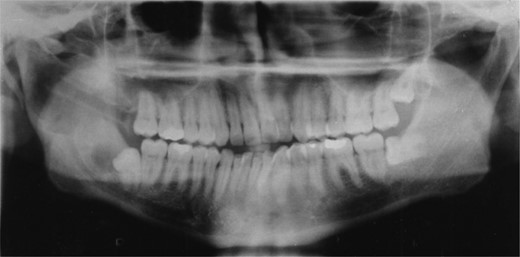

A decision was made to decompress the lesion to try and shrink the cystic space, encouraging bony infill. Over the following 3 months the patient underwent a further three re-packing procedures with irrigation of the cavity. The site of the cyst and difficulty of access necessitated general anaesthesia. The patient was admitted on one occasion for intra-venous antibiotics following an acute infective episode affecting the area. During the third operative procedure a split nasopharyngeal tube was inserted into the cyst cavity and sutured in position (Fig. 2). The patient was encouraged to flush the cavity clean through the tube drain.

Demonstrates bony infill with the nasopharyngeal tube in place.